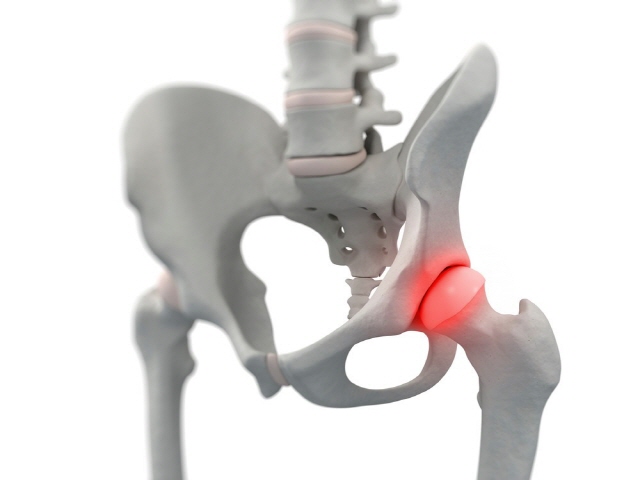

4. 고관절 통증 증상 - 대퇴골두 무혈성 괴사

정상적인 대퇴골두가 둥근 탁구공 모양이라면, 무혈성 괴사가 진행된 경우에는 표면이 납작해지거나 형태가 변형되어 보입니다. 뼈에 혈액 공급이 원활하지 않으면 대퇴골두 조직이 괴사하면서 점차 무너져 통증과 보행 장애를 초래합니다. 원인으로는 과다한 음주나 스테로이드 과용 등이 연관된다고 알려져 있으며, 주로 30~50대에서 발병하는 경우가 많습니다. 초기에는 고관절 부위의 통증이 주 증상이며, 병이 진행되면 보행이 어려워지고 다리 길이 차이 같은 변형이 나타날 수 있습니다.